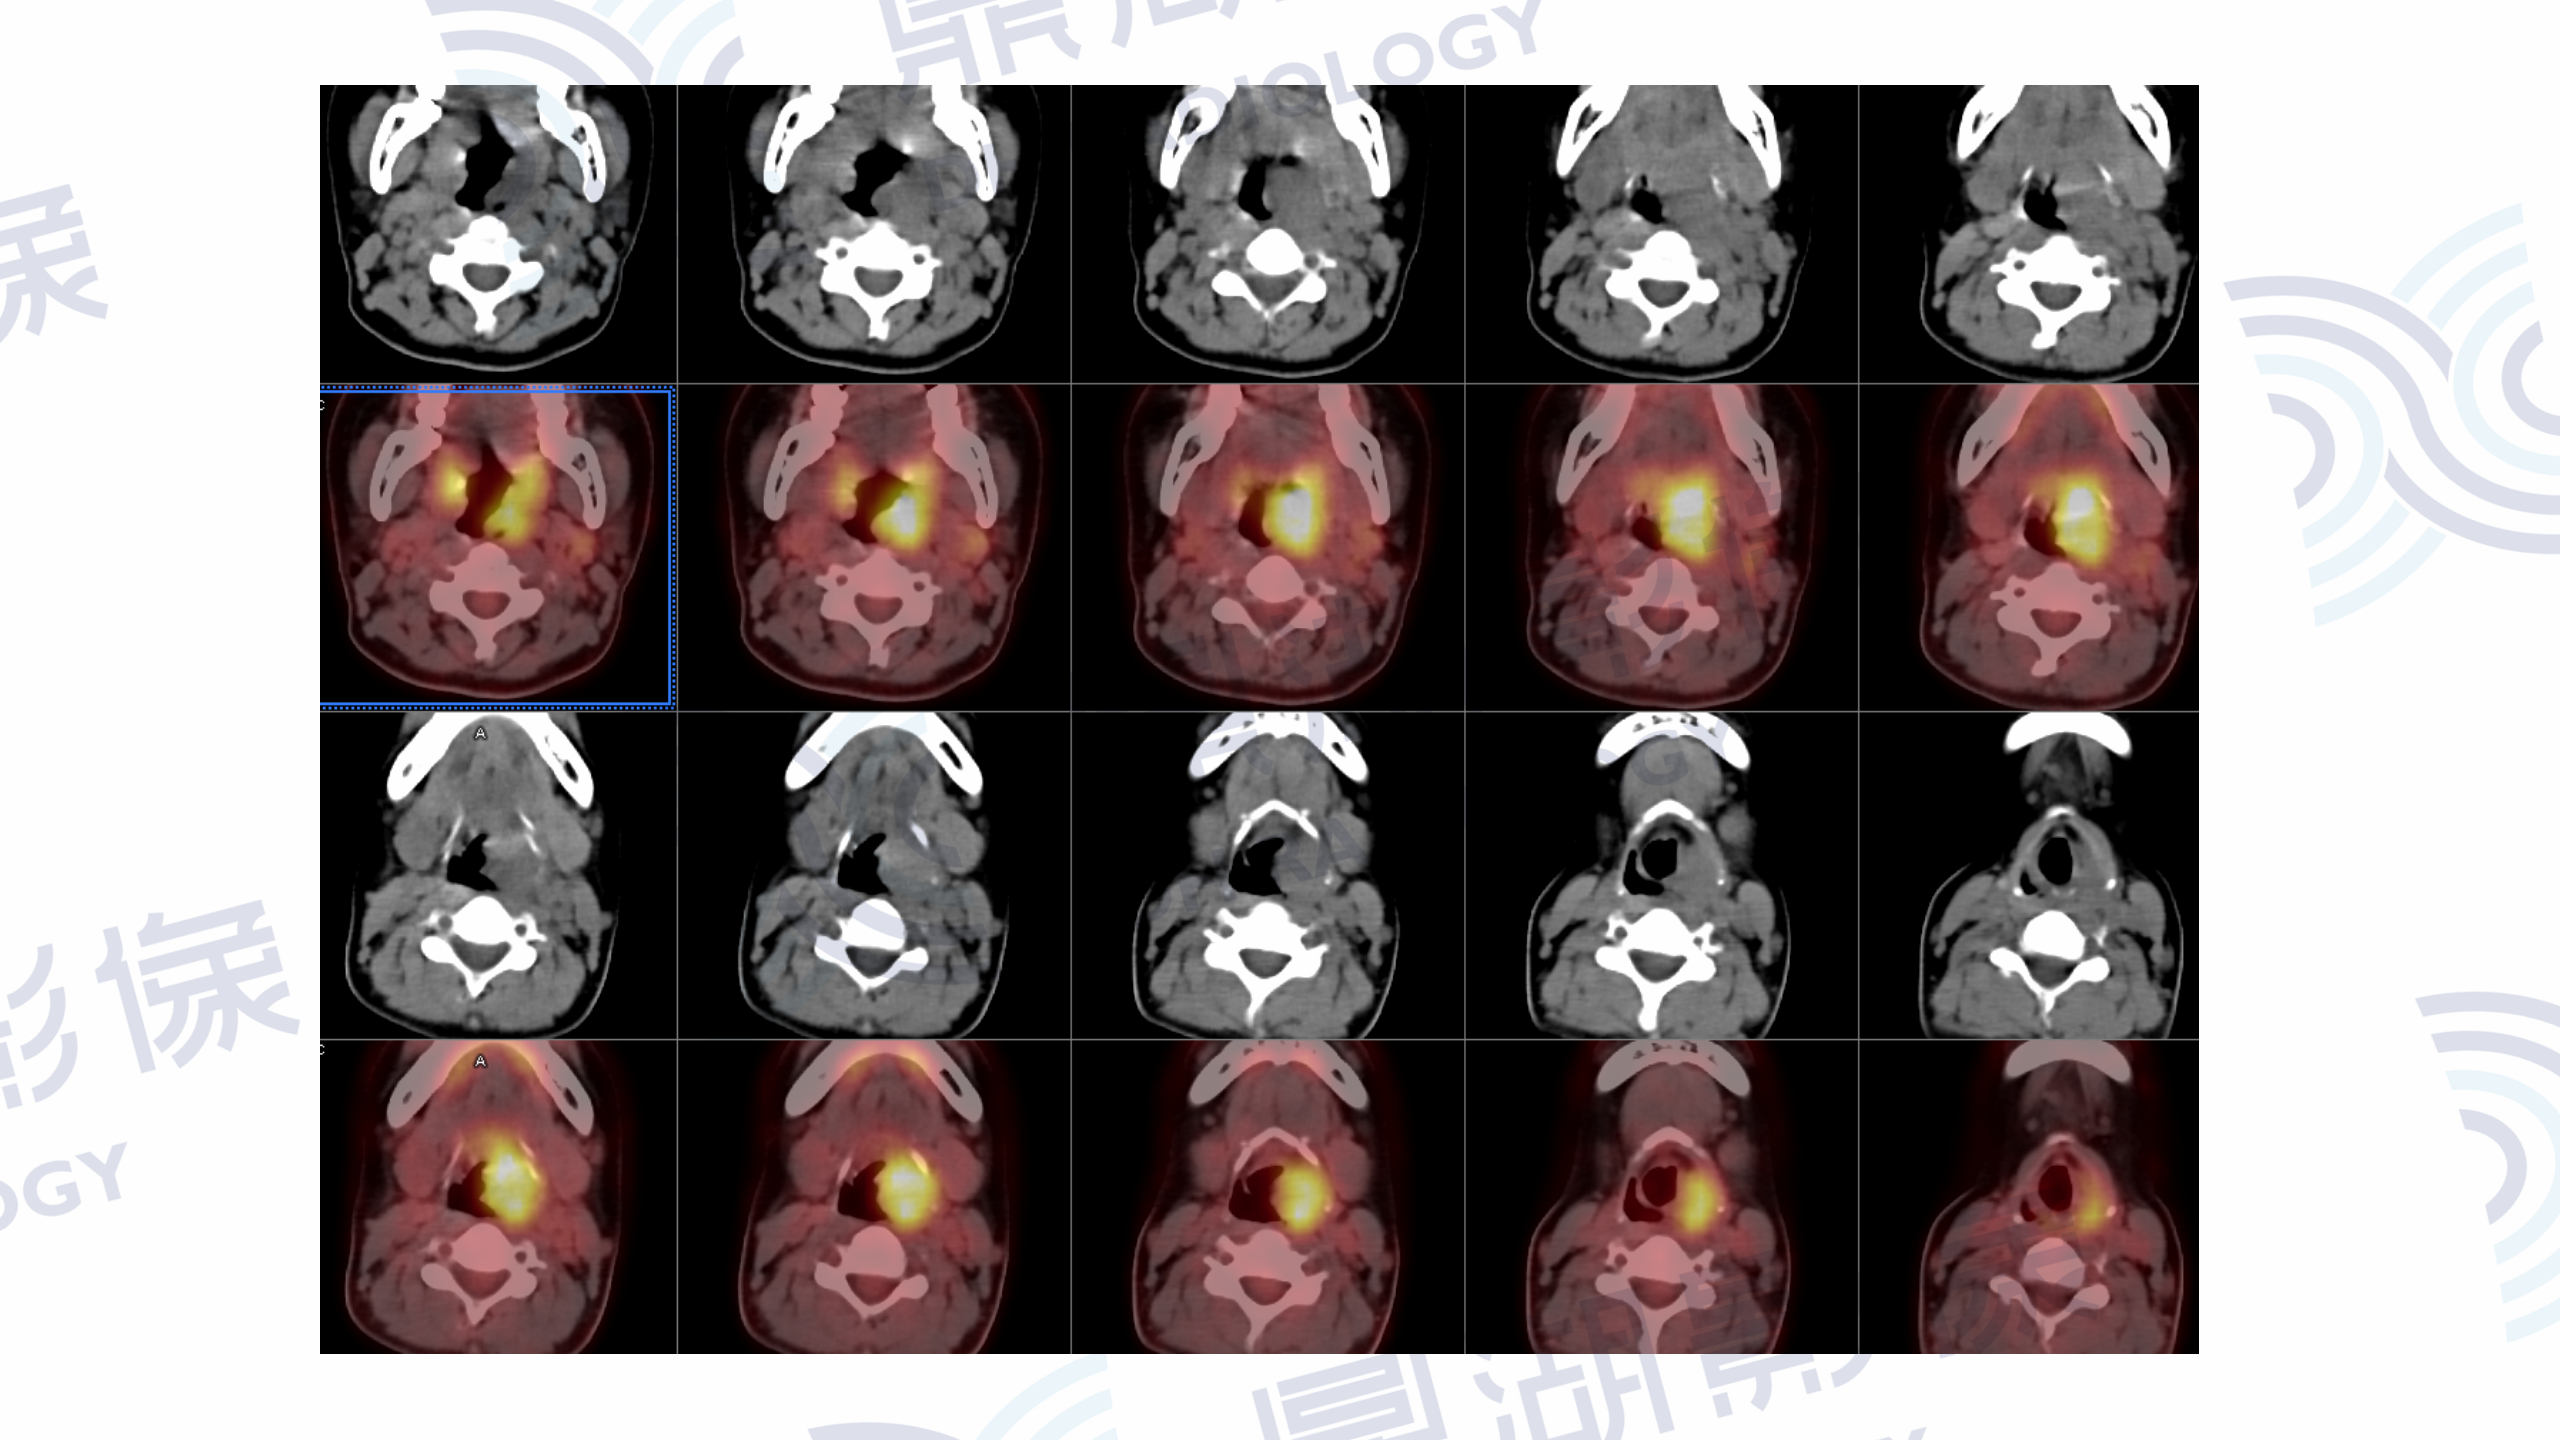

女  23岁  咽部不适1周,喉镜检查示咽部新生物,无疼痛发热等症。血常规实验室检查未见明显异常。本中心MR检查提示口咽恶性肿瘤,疑淋巴瘤可能,于本中心进一步行PET/CT检查。

MR增强检查提示:口咽左侧壁至左侧声门上不规则软组织肿块,病灶突入咽腔,信号均匀,T1WI呈等信号,T2W呈稍高信号,DWI呈高信号,增强扫描呈轻度均匀强化,左侧杓状会厌皱襞水肿,左侧梨状窝消失。

PET/CT提示:口咽左侧壁至左侧声门上软组织肿块,FDG摄取增高,SUVmax=13.1。

口咽部活检病理为淋巴组织增生,IgG4浆细胞浸润阳性。